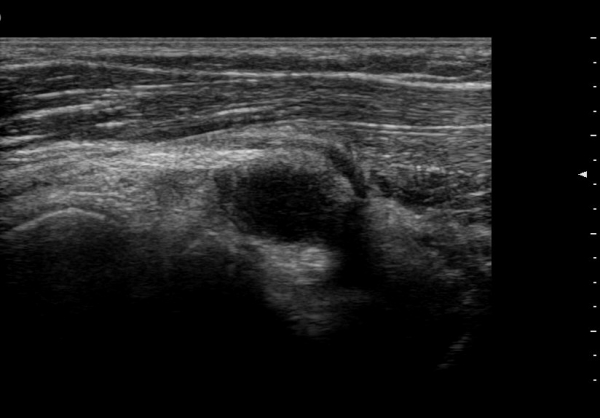

ŽÃËÀÚ¸¦ ¸»´ÜÀ¸·Î À̵¿ÇÏ´Ï ¿ä°ñµÎ ºÎÀ§¿¡¼­ Àú¿¡ÄÚ ³¶Á¾ÀÌ Èİñ°£½Å°æºÐÁö¸¦ Ç¥ÃþÀ¸·Î

ÀüÀ§½Ã۰í ÀÖ´Ù(±×¸² 2, 3,)

Á¾´Ü¸é°Ë»ç¿¡¼­ Àú¿¡ÄÚ ³¶Á¾ÀÇ Ç¥Ãþ¿¡¼­ Èİñ°£½Å°æºÐÁö°¡ ÀüÀ§µÇ¾î °üÂûµÈ´Ù(±×¸² 4, 5, 6).